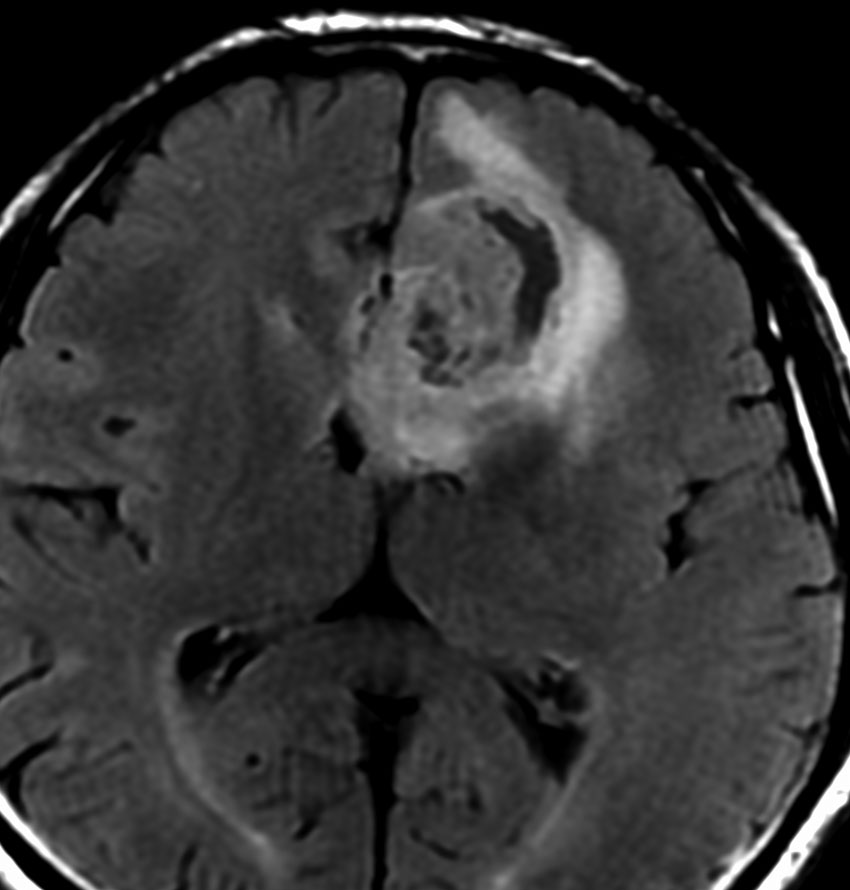

5年後にいきなり激しい再発を生じました。再発部位は,放射線照射野外 out-of-fieldの前頭部帯状回でした。手術前に急速に増大して,画像所見も初回と全く違いました。摘出後の病理は,IDH1/2 wild type, 1p/19q intact, ATRX negative, MGMT met negative, MIB-1 40%という典型的な膠芽腫の所見でした。

この例とは異なって,退形成性星細胞腫の再発時には,IDH mutantのままの方が多いです。もしかすると先行した放射線誘発膠芽腫かもしれません。